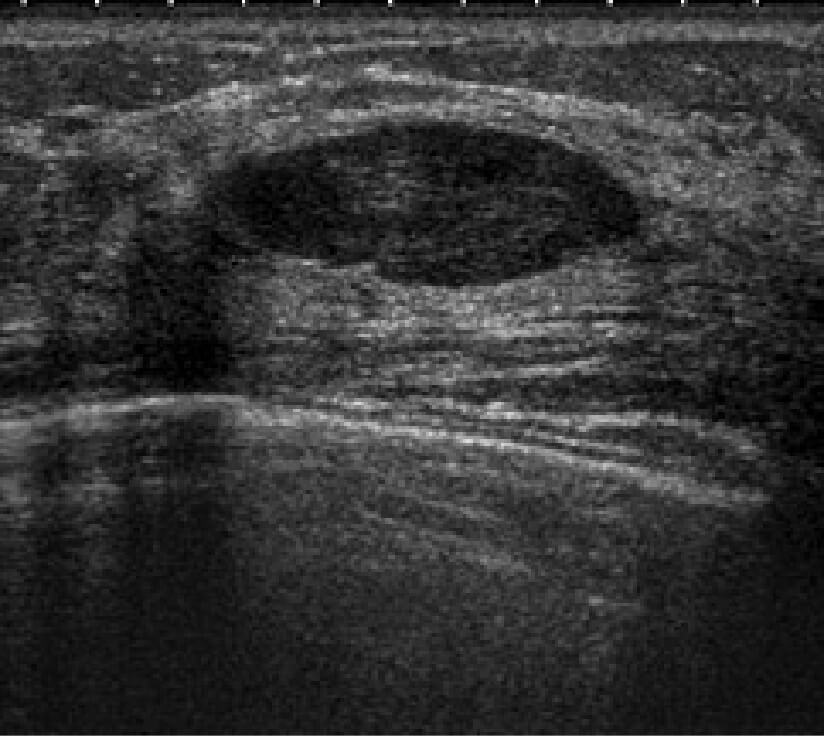

乳房超音波検査

良性腫瘤の症例